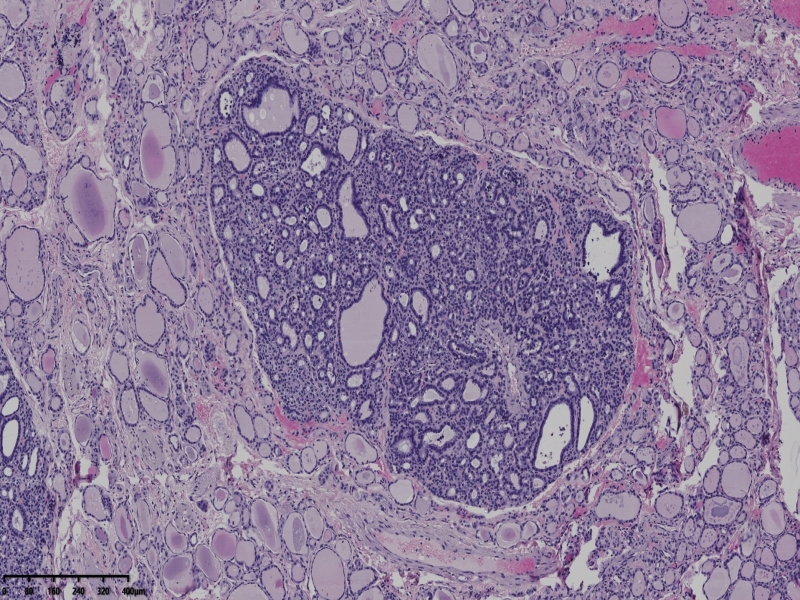

男、69、甲状腺左叶肿物,部分为囊性,囊内可见乳头状结构,上皮核重叠,没有核沟,没有毛玻璃样改变,没有核内假包涵体。255427

部分区域瘤组织与周围甲状腺组织分界明显,没有包膜样结构,滤泡结构为主,细胞异型明显。

会诊结果:(左叶甲状腺近峡部)甲状腺肿瘤,考虑为具有RAS核的乳头状癌,建议免疫组化及基因检测。